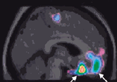

Merged PET-MRI brain section illustrating changes in cerebral blood flow during movement visualization. From: Lafleur, M. F., et al., 2002. Motor learning produces parallel dynamic functional changes during the execution and imagination of sequential foot movements. Neuroimage. 16, 142-157.